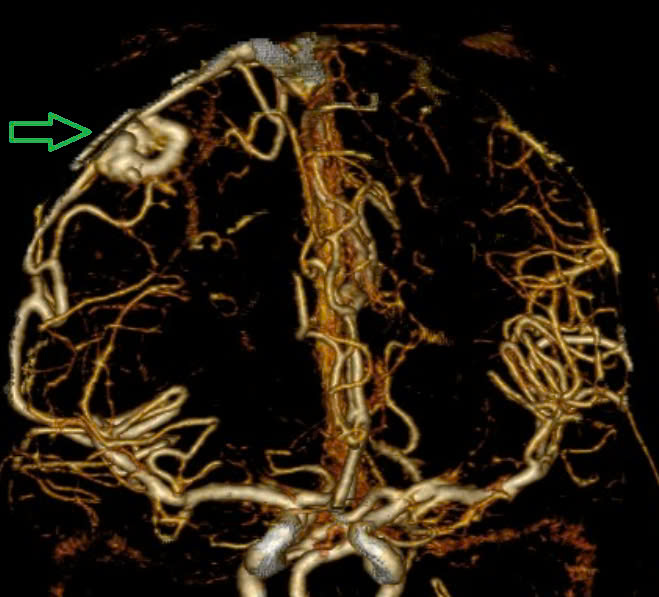

Hình ảnh chụp MSCT mạch não cho thấy chảy máu não thuỳ đỉnh phải, chảy máu não thất do vỡ AVM.